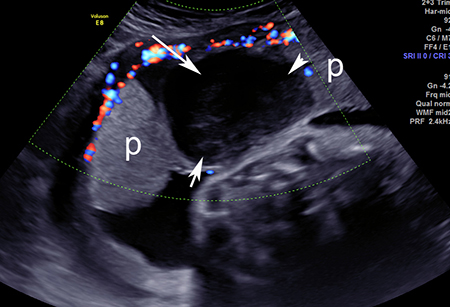

Imagem de ultrassonografia de descolamento da placenta: a placenta normal está marcada com 'p'; área de descolamento indicada por setas brancas

Do acervo de Dr Y Oyelese; usado com permissão